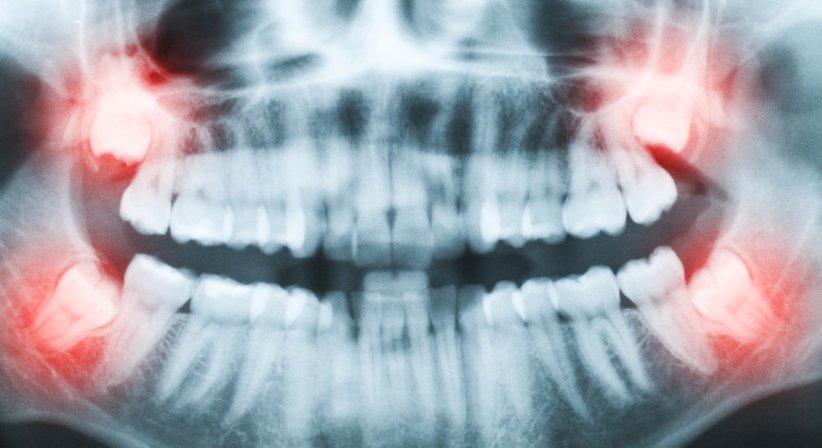

Bei vielen Menschen brechen die Weisheitszähne aufgrund von Platzmangel nur teilweise oder gar nicht durch. Zudem kann ein Weisheitszahn verlagert im Kieferknochen liegen.

Retinierte und verlagerte Weisheitszähne können u.a. zu einer Verschiebung anderer Zähne sowie Zahnfleischentzündungen führen, Gesichts-, Ohr- und Kiefergelenksschmerzen verursachen und in seltenen Fällen auch Zysten hervorrufen.

Wenn Weisheitszähne solche oder ähnliche Beschwerden bereiten oder erwarten lassen, ist eine operative Entfernung zu empfehlen. Die Entfernung eines Weisheitszahnes wird selbstverständlich schmerzarm und routiniert durchgeführt.